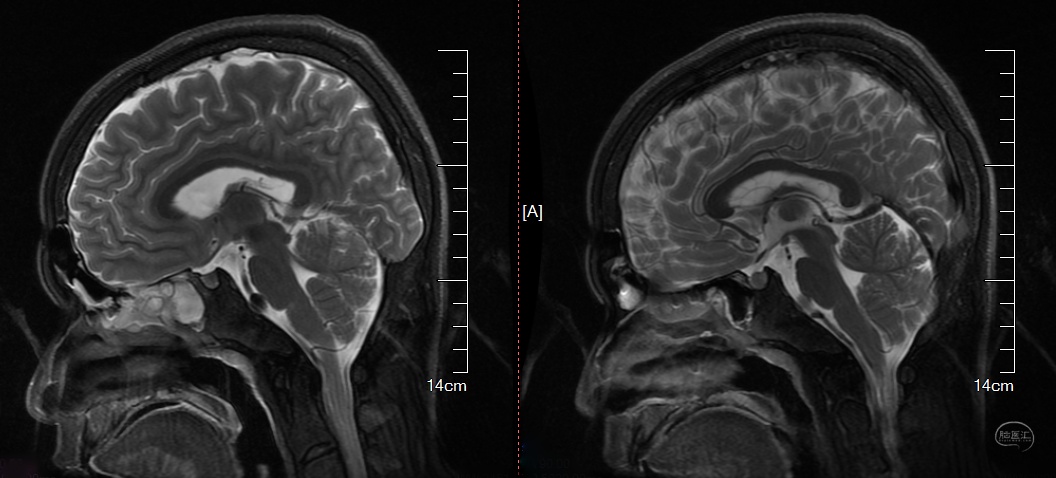

T2: